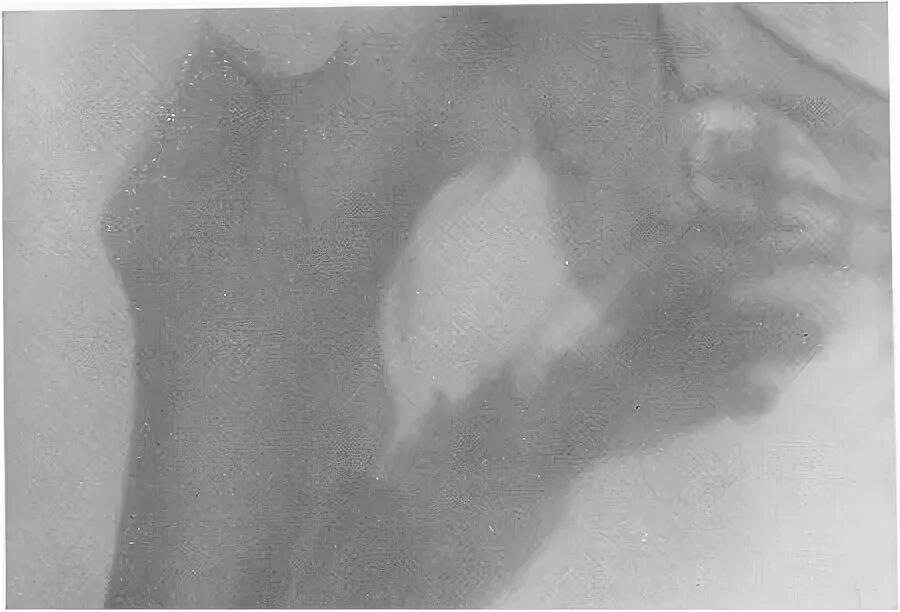

Мкб миозит мышц